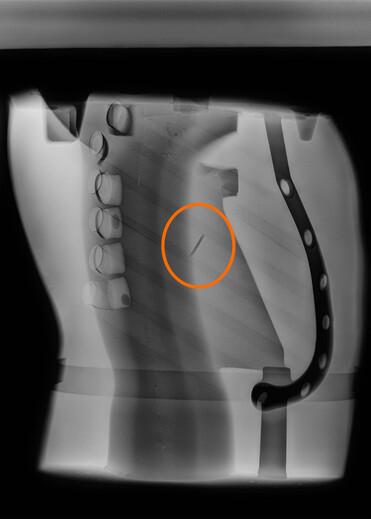

Direkt nach einem Crashtest können durch medizinisches Röntgen Beschädigungen an Knochen- und Gewebeteilen des PRIMUS-Dummys sichtbar gemacht werden. Durch diese direkten Einblicke können so Rückschlüsse auf reale Verletzungen gezogen werden und ermöglichen darüber hinaus eine Einstufung in die vereinfachte Verletzungsskala (Abbreviated Injury Scale (AIS)).

Auswertung der Röntgenbilder, PRIMUS breakable

Beispiel der technische Auswertung anhand des PRIMUS breakable

Technische Obduktion - Fotodokumentation der Verletzungen

Gutachten über die technische Obduktion (AIS-Auswertung)